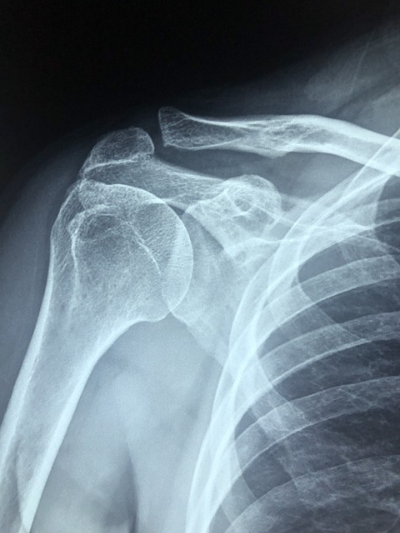

어깨를 감싸고 있는 근육과 어깨뼈가 충돌이 일어나면서 나타나는 증상으로

팔을 움직이면 정상적으로 회전을 해야 되지만 충돌이 일어나게 됩니다. 팔을 어깨보다 높게 들거나, 어깨 속에 결림이 있다면 어깨충돌증후군을 의심해야 됩니다.

단순 근육통이 아니라, 회전근개 파열로 어깨 질환의 시작이라고 할 수 있습니다.

회전근개는 어깨 관절을 지탱하고, 팔을 잘 움직이게 하는 것입니다.